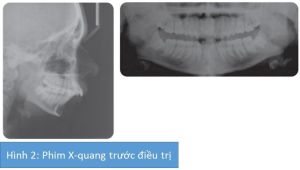

Phân tích case: Niềng răng và phẫu thuật kéo giãn xương hàm dưới cho bệnh nhân bị hô đáng kể

Bệnh nhân nữ 16 tuổi có khớp cắn hạng II tiểu loại 1 trên nền xương hạng II khá trầm trọng kết hợp với xương hàm dưới lùi và tỉ lệ theo chiều đứng trung bình. Độ cắn chìa tăng đến 12 mm và độ cắn trùm bình thường nhưng không chạm khớp. Tương quan răng hàm hạng II 2 bên và đường giữa hàm dưới lệch trái 1 mm. Chen chúc nghiêm trọng cung hàm dưới và chen chúc mức độ nhẹ ở hàm trên.